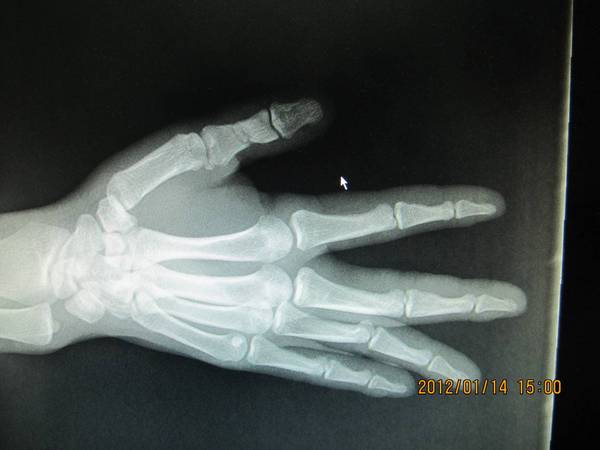

RE: 拇指近节缺损性离斷--邻指指动脉岛状皮瓣桥接再植术后50

术后50天复查,拔出克氏针,知道患者继续进行功能锻炼。